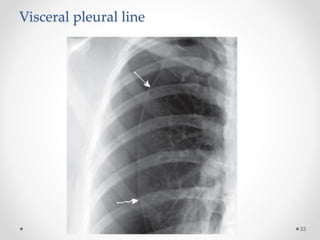

Visceral pleural line

DD of visceral pleural line

Skin fold:

• Positive mash band (optical edge enhancement).

• Extend beyond the chest wall.

• Lung markings extend beyond it.

Scapular edge